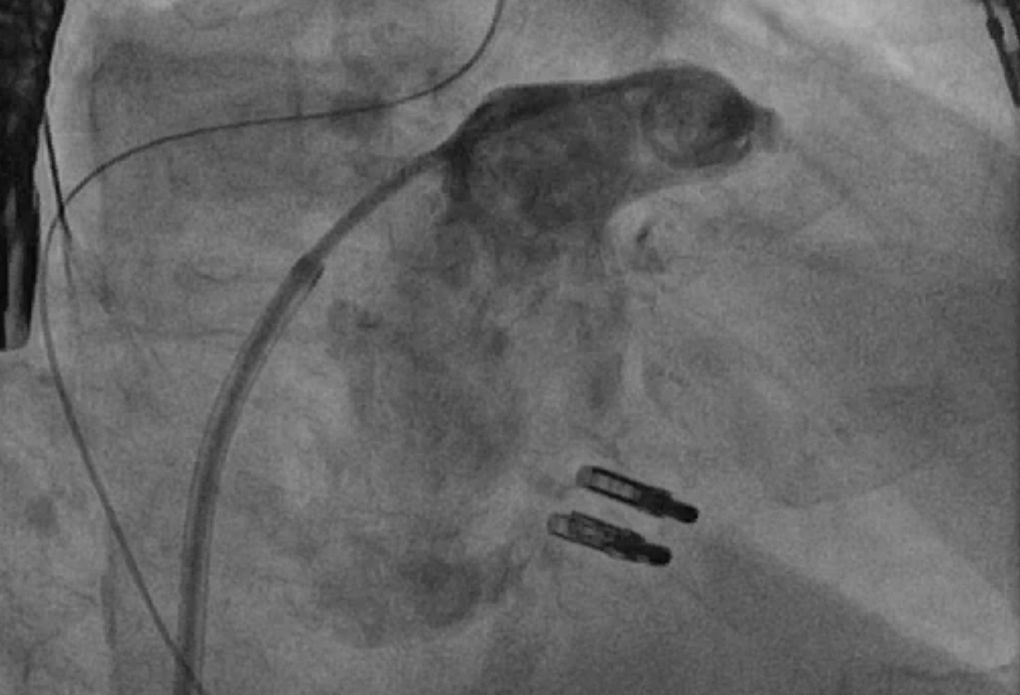

Bei Kontraindikationen für eine orale Antikoagulation, z.B. nach einer schweren Blutung,  kann das linke Vorhofohr mit einem gleichwertigen thrombembolischen Schutz vor Schlaganfällen verschlossen werden.

In unserem Herzkatheterlabor  bieten wir die Möglichkeit das linke Vorhofohr mit verschiedenen Okkludermodellen, je nach Anatomie, erfolgreich zu verschließen.